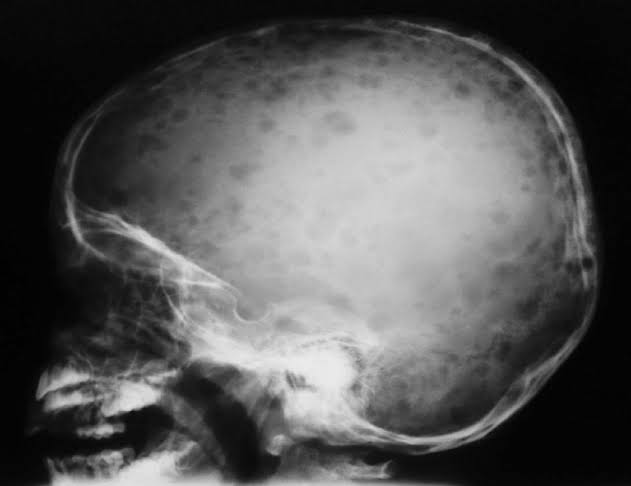

Image :- Google